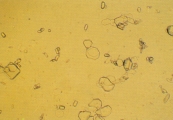

Кальция карбонат может кристаллизоваться в моче лошадей, кроликов, коз, образуя большие желто-коричневые или бесцветные сфероиды с радиальной исчерченностью, или маленькие кристаллы круглой, овальной или гантелеобразной формы (рис. 2 и 3). У собак и кошек эти кристаллы обычно не обнаруживаются. Если в моче обнаруживается гантелеобразный кристалл, то это скорее кальция оксалат моногидрат.

Рис. 2. Микрофотография кристаллов кальция карбоната в мочевом осадке 7-летней кобылы (не окрашено, увеличение Х160